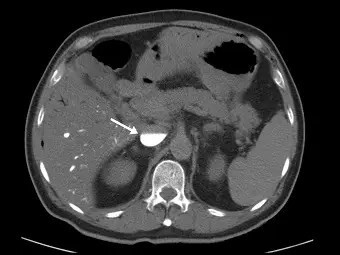

患者接受電腦斷層檢查,由上臂注射對比劑,於檢查中心臟驟停( sudden cardiac arrest ),上腹部某血管呈現對比劑與血液的水平面( contrast-blood level ),下圖箭號所指之解剖構造為何?

本題的核心概念為「對比劑依賴性鬱積徵象(Dependent contrast pooling sign)」或稱為「下腔靜脈對比劑分層徵象(IVC contrast level sign)」。當病患在進行靜脈注射對比劑的 CT 檢查過程中,若發生心因性休克或心臟驟停(sudden cardiac arrest),由於缺乏心臟向前的推動力,比重較高的含碘對比劑會受到重力影響而產生異常的靜脈逆流與沉澱現象。

觀察此張上腹部的無顯影/早期異常顯影的軸切面(axial)CT 影像:

- 解剖構造定位:影像中央偏下方為脊椎(Vertebral body)。脊椎正前方偏左側的圓形管狀構造為「腹主動脈(Abdominal aorta)」,此處呈現低密度,表示對比劑尚未到達左心與動脈系統。

- 箭號指引處:脊椎前方偏右側的粗大血管即為「下腔靜脈(Inferior vena cava, IVC)」。

- 異常影像特徵:箭號所指的下腔靜脈內,出現了一條非常清晰的水平線。血管下半部(靠背側,即仰躺時的重力垂下處)呈現極高密度的亮白色,這是因為含碘對比劑沉積於此;血管上半部(靠腹側)則為密度較低的血液。這種現象即為題幹所描述的「對比劑與血液的水平面(contrast-blood level)」。